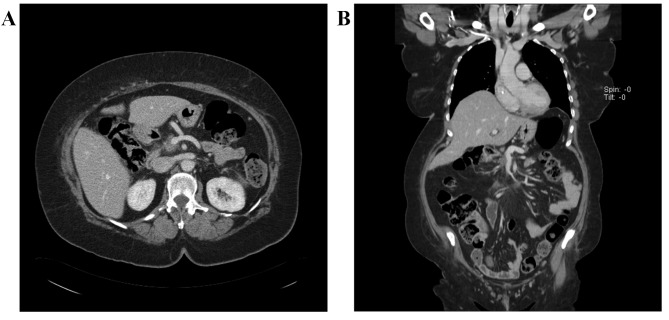

In September 2014, a 58-year-old female patient was presented at the Lugano Regional Hospital (Lugano, Switzerland) with long-lasting diabetes, abdominal pain and weight loss. The Eastern Cooperative Oncology Group performance status was 1, and laboratory parameters were normal, with the exception of carbohydrate antigen (CA) 19–9, which was 149.2 U/ml (normal range: <35.4 U/ml), and carcinoembryonic antigen, which was 59.1 ng/ml (normal range <3.0 ng/ml). A computed tomography (CT) scan revealed a 3.7-cm mass in the pancreatic head, encasing the porto-mesenteric axis ≥180°, with narrowing and almost complete short segment occlusion of the SMV, and superior mesenteric artery (SMA) abutment (Fig. 1A and B). There was no evidence of lymph node involvement or visceral metastatic spread. The result of an endoscopic ultrasound-guided fine needle biopsy was concordant with adenocarcinoma, and the patient was diagnosed with BRPAC.

Figure 1.

(A) Axial plane and (B) coronal plane computed tomography scan prior to neoadjuvant chemotherapy, showing radiological signs of a borderline resectable lesion: e.g. Encasement/short segment occlusion of the superior mesenteric vein and tumor abutment of the superior mesenteric artery.